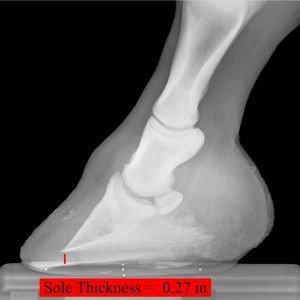

> Obrázek 5: Koně s tenkým chodidlem jsou mnohem náchylnější k onemocnění hnilobou kopyt, zejména tehdy, když žijí ve vlhkém prostředí. Já obecně ráda vidím, že chodidlo tvoří přibližně 1,25 cm (0,5 palce) silná vrstva kvalitní rohoviny. Pamatujte si, že to je to jediné, co poskytuje oporu kopytní kosti, a působí jako bariéra proti změnám teploty a průniku bakteriální infekce.

Ujistěte se, že má váš kůň pravidelně a správně upravovaná kopyta. Správná kopytní rovnováha pomáhá vyhnout se mnoha problémům se zatěžováním kopyt. Slabá kopyta jsou více náchylná k infekcím. Zajistěte, aby chodidla vašeho koně byla dostatečně hluboká. Koně s tenkým chodidlem, a to především ve vlhkém prostředí, jsou mnohem náchylnější k infekcím. Udělejte preventivní rtg snímky, ty vám vždy pomohou posoudit skutečný stav kopyt, např. hloubku chodidla.